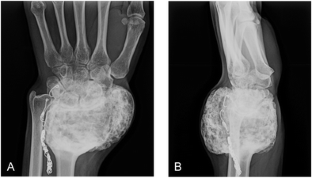

Fig. 1